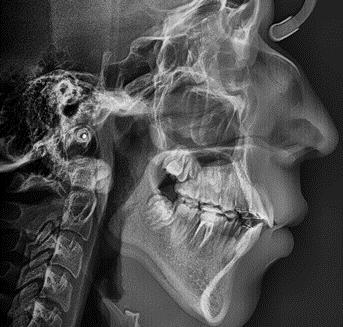

En la radiografía lateral de cráneo se ve el diagnósitico: clase II esqueléti ca, con crecimiento hiperdivergente, mordida profunda anterior (Figura 4).

En la radiografía panorámica se observa 28 piezas dentales, con un diastema en los incisivos centrales (Figura 5).